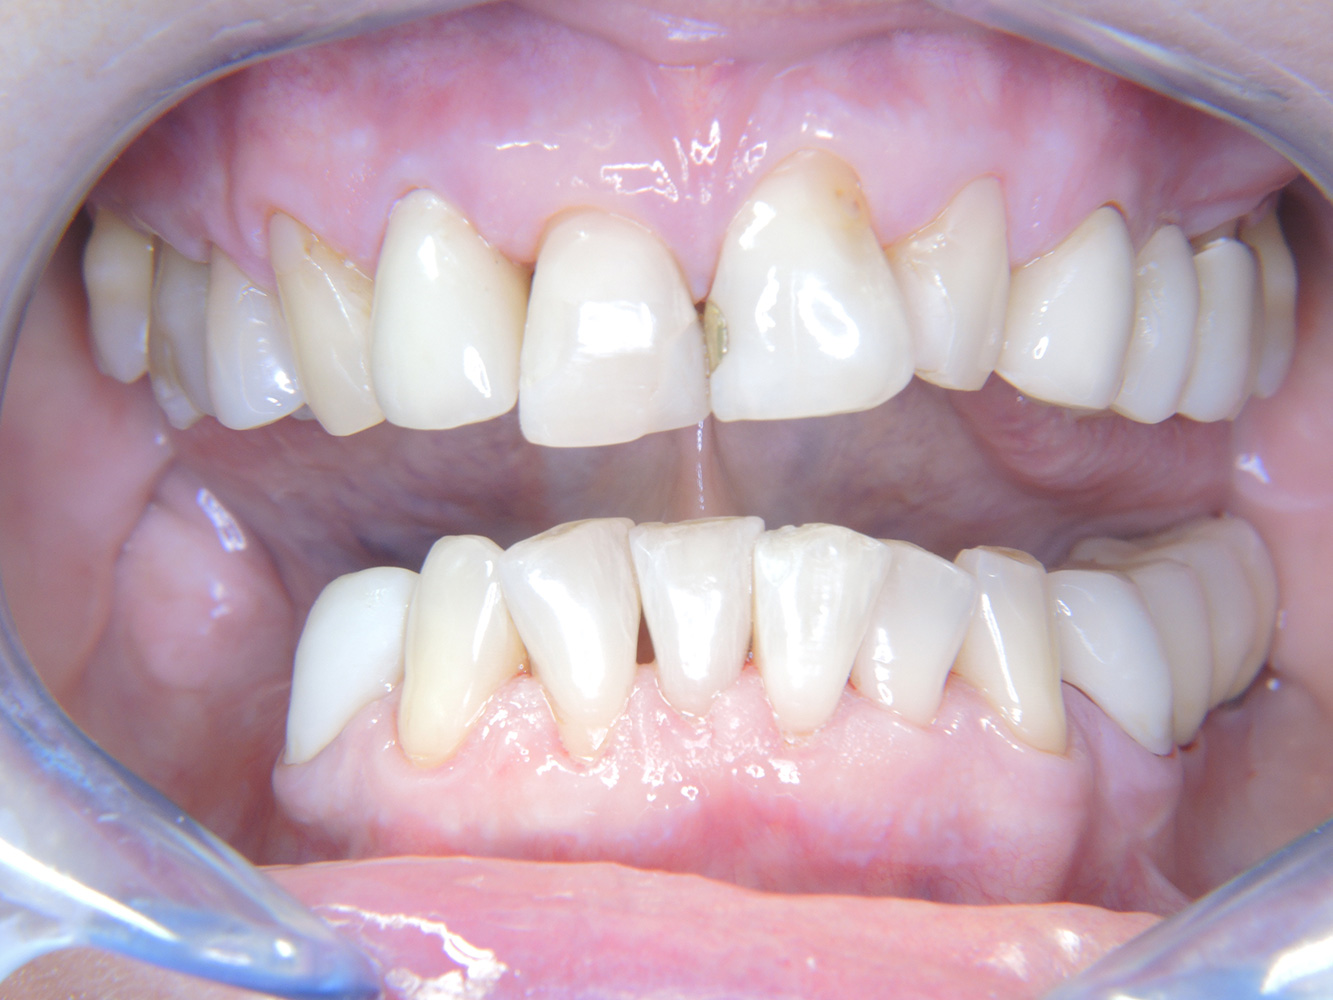

The 68-year-old patient has no general health conditions and is not taking any medication that may be relevant to her oral health, and her lifestyle does not pose any particular risk. The patient has two dental implants (3rd quadrant, for five years) and a previous case of periodontal disease (stage IV, grade B periodontitis) with tooth loss. Currently the periodontal conditions are stable. However, periodontitis significantly increases the biological complications of implantations and there is a risk of implant loss (21). Four recommendations can be determined for the prophylaxis session.

As the patient does not have any particular risk factors with specific dental implications, the requirements determined from her current state of oral health are crucial. Here, it is recommended that a thorough assessment of periodontal condition be carried out once a year. This will ensure that any potential progression of the previous periodontal disease or development of peri-implantitis can be responded to in good time.

Because the patient has implants and a history of periodontal disease, she is at risk of developing peri-implantitis. It is therefore recommended that she attend a recall session every three to four months.